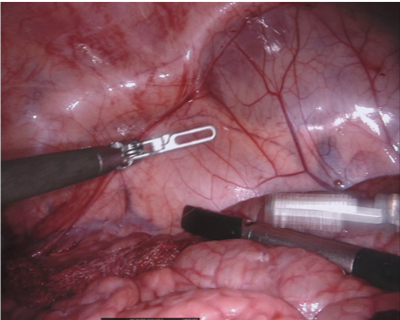

Our challenge was made up of 3 sub-problems. The first was binary instrument segmentation, where each frame was separated into da Vinci Xi instruments and a background class, which contained an ultrasound probe, surgical clips and porcine tissues. The second task was instrument part segmentation, where we scored the participants on whether they could correctly segment each articulating part of the instrument (see Fig. 3). Our final task was to segment and classify the instruments (see Fig. 4).

We provided the first 225 frames of 8 sequences as training data and kept the last 75 frames of those 8 sequences as test data. 2 of the full 300 frame sequences were kept as test sequences. Test labels were kept hidden from the participants. Our datasets contain 7 different robotic surgical instruments. The Large Needle Driver, Prograsp Forceps, Monopolar Curved Scissors, Cadiere Forceps, Bipolar Forceps, Vessel Sealer and additionally a drop-in ultrasound probe, which is typically held in the jaws of the Prograsp Forceps instrument. Samples from the training datasets are depicted in Fig. 2 and examples of the different instrument types are shown in Figure 3 and 4.